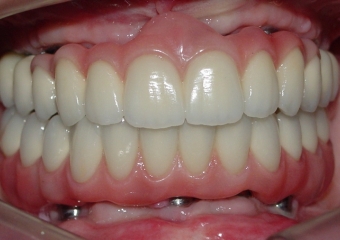

Imagens finais do caso terminado em agosto de 2010

Sorriso final